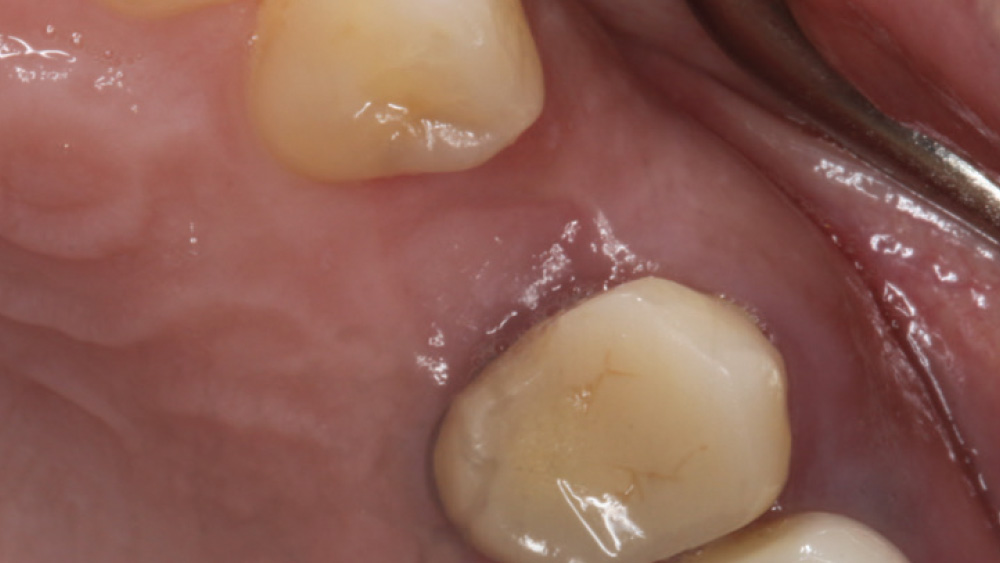

In contrast, with a flapless procedure, a tissue punch is used to gain access to the bone through the gingiva, minimizing postoperative discomfort by eliminating incisions in the mucosal tissue. Whenever mucosal tissue is incised, prostaglandin and histamine are released, resulting in potential postoperative swelling and pain. Therefore, when there is an adequate width of attached gingiva on the facial aspect of an implant site, a flapless procedure may be indicated, eliminating any suturing requirements.

The following case, which I performed alongside Dr. Stephanie Tilley of Pensacola, Florida, illustrates the use of both surgical techniques for the same patient, who presented with edentulous spaces in the areas of both right and left maxillary first bicuspids. Due to varying soft-tissue volume on each side of the arch, implant surgery was performed using a flapless procedure for one site, while the attached gingiva was reflected to expose the available hard tissue for the other. As a result of proper site evaluation, treatment planning and restorative-driven implant placement, both surgical techniques led to successful outcomes for the patient.